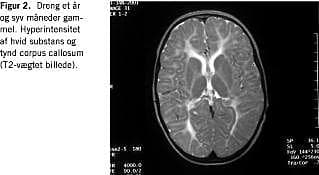

MR-skanningsfund

MR-skanning af cerebrum ved SS viser hypoplasi af corpus callosum og hyperintensitet af den subkorticale hvide substans (indikerer defekt myelinisering) (Figur 1 og Figur 2 ). Svært afficerede patienter har atrofi af cortex, hjernestamme og cerebellum samt cerebellar hypomyelinisering og periventrikulær hyperintensitet [8, 9].